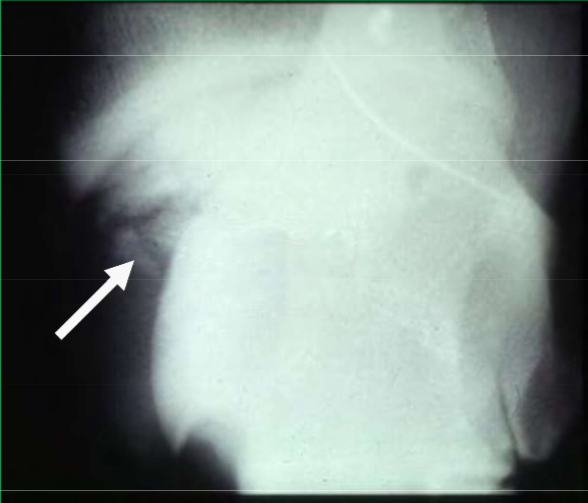

What is this lesion

OCD of the distal intermediate ridge of the tibia in the hock